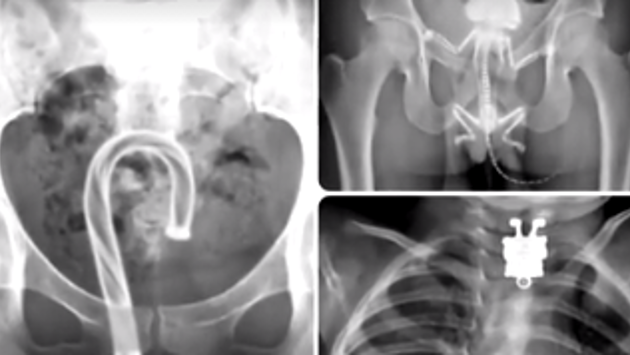

Самые странные вещи, найденные рентгеном

Говорят, удивить опытных медиков крайне сложно. Однако, оказывается, рентгеновские снимки некоторых пациентов поражают воображение даже самых опытных специалистов.

Так, в организме человека могут оказаться и 10-сантиметровые ножницы, и стрела, и даже живая ель. Смотрите видео, чтобы узнать о самых удивительных находках, проявившихся на рентгеновских снимках.